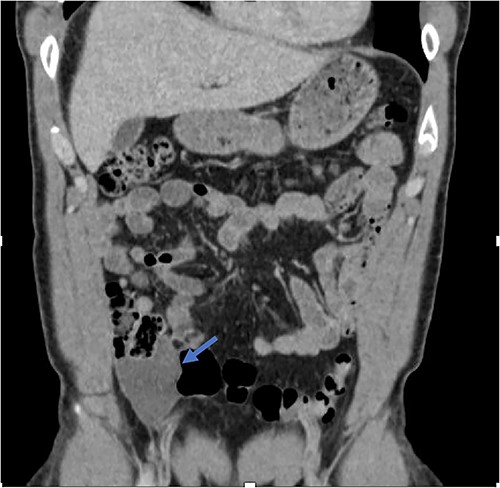

An active 41-year-old male with no significant past medical, surgical, or significant family history presented to the emergency department for evaluation of right lower quadrant abdominal discomfort that started three days prior to arrival. He did not report any associated trauma or systemic signs of disease, including fever, chills, night sweats, or weight loss. On physical exam, the patient did not appear to be in any distress and was otherwise well-appearing. He had mild right lower quadrant tenderness on palpation without rebound, guarding, or peritoneal signs. Diagnostic studies included a contrast-enhanced CT scan of the abdomen and pelvis, which revealed two fluid collections in the region of the appendix and the cul-de-sac, measuring ~21 Hounsfield units, without evidence of active inflammation (Fig. 2). His labs were otherwise unremarkable. Given these findings, he was initially treated for perforated acute appendicitis with abscess. Antibiotics were started, and the decision was made to drain the fluid collection. Diagnostic laparoscopy or drainage of the fluid collection by interventional radiology was not pursued given the risk of potentially seeding a malignant process. Since the patient continued to have persistent symptoms and the differential diagnosis included lesions with malignant potential, the decision was made to proceed with exploratory laparotomy for both diagnostic and therapeutic purposes.

Fluid collection is present in the cul-de-sac that measures 5.8 × 4.8 × 2.9 cm (blue arrow).